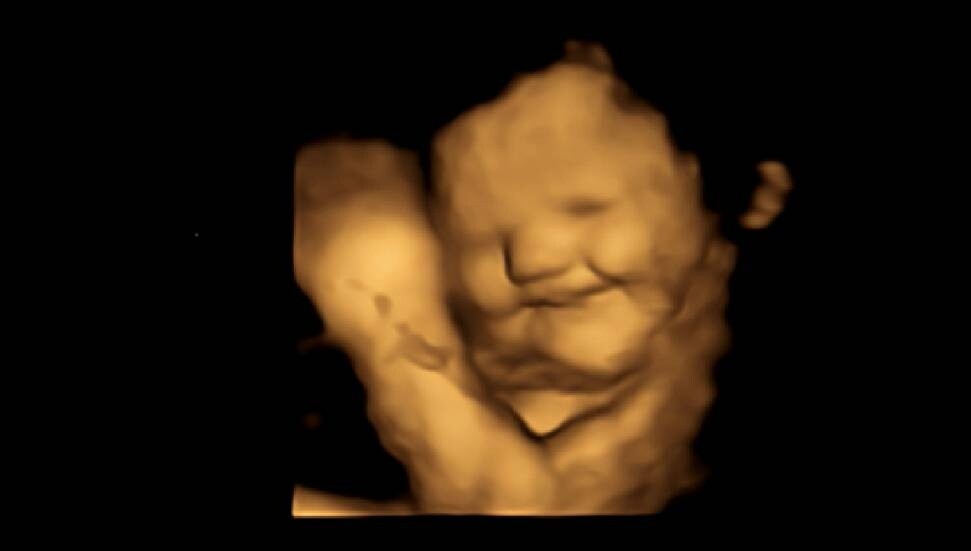

Bunun ardından fetüslerin, gülme ve ağlamaya benzeyen yüz hareketlerinin analizi gerçekleştirildi.

Bulgular fetüslerin, karalahana kapsülü tüketildiğinde yüzünü ekşittiğini gösterdi. Anne havuç tozu aldığında fetüs, karalahana tozu kullanıldığında ya da hiçbir toz alınmadığındaki zamana göre yaklaşık iki kat fazla gülen surat ifadesi takındı.

Ultrason taramasından 20 dakika önce bir gruptan toz karalahana, diğer gruptan toz havuç tüketmeleri istendi.